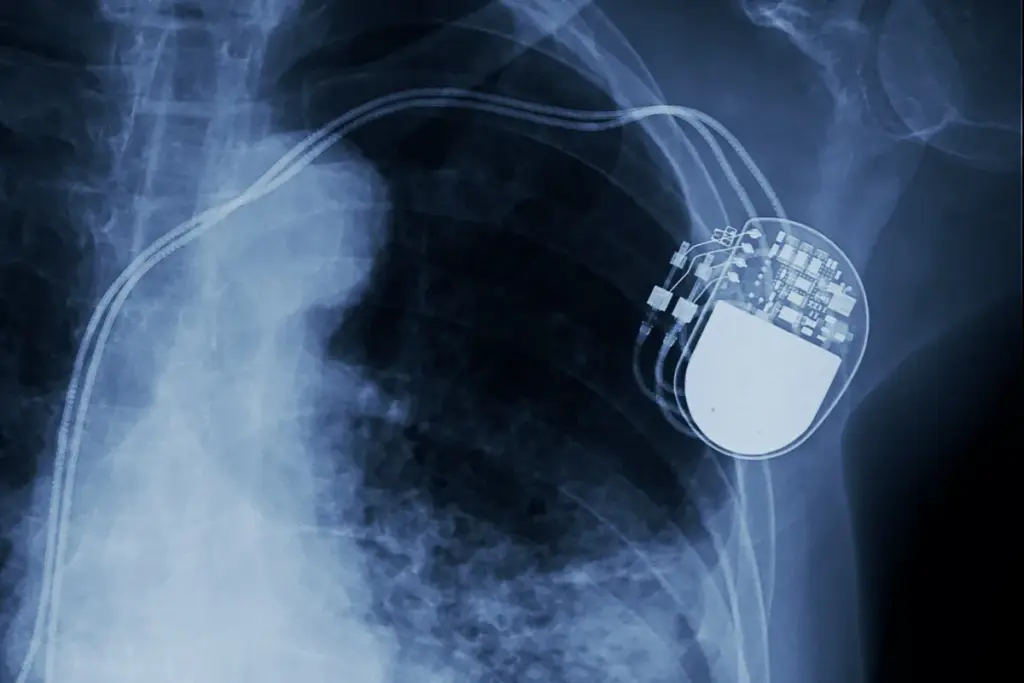

Understanding Implantable Cardioverter-Defibrillators (ICDs)

Implantable Cardioverter-Defibrillators (ICDs) are advanced medical tools. They help treat serious heart rhythm problems. These devices are key for those at risk of sudden cardiac death.

What is an ICD and How Does It Work?

An ICD is a small device put under the skin, usually in the chest. It watches the heart’s rhythm all the time. If it finds a dangerous rhythm, it sends electrical therapy to fix it.

This therapy can be a gentle pace or a shock to correct the rhythm. The device has leads that go into the heart through a vein. These leads connect to the ICD generator, which analyzes the rhythm and delivers therapy.